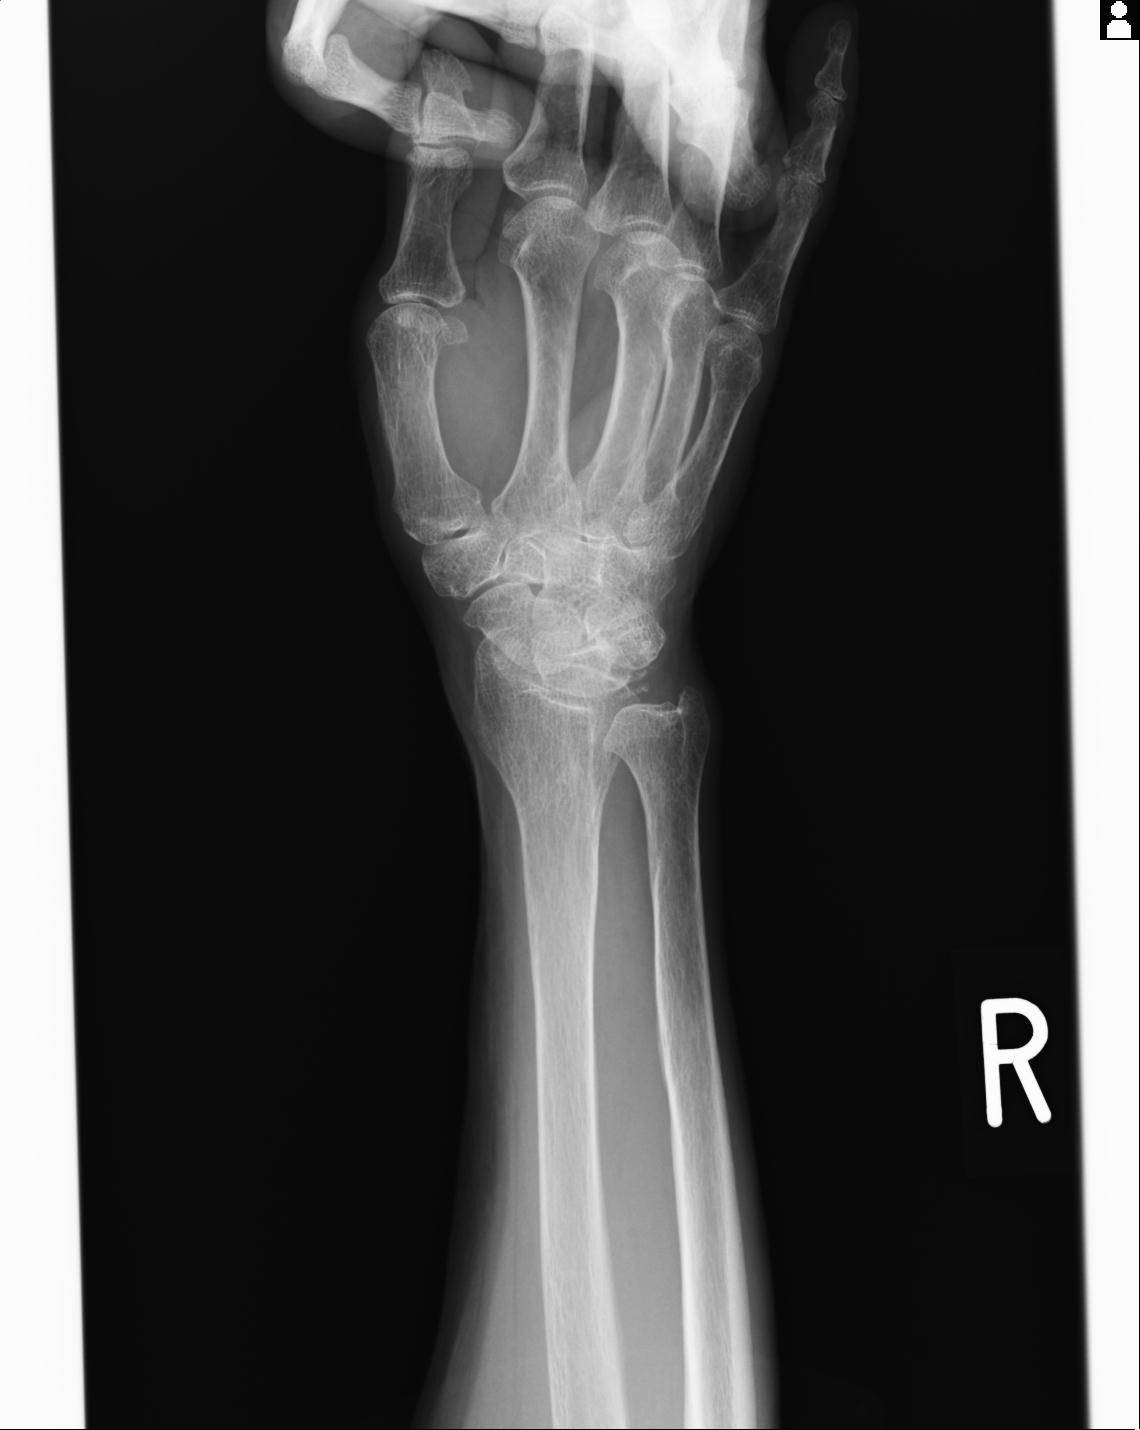

46666 1/23 両股正面+軸と右手関節 2R 76歳女性 右橈骨遠位端

50435 1/4 1/15 手関節 4R 17歳女性 右橈骨遠位端

101290 1/4 5/21 5/20 手関節 2R 17歳男性 橈骨遠位端